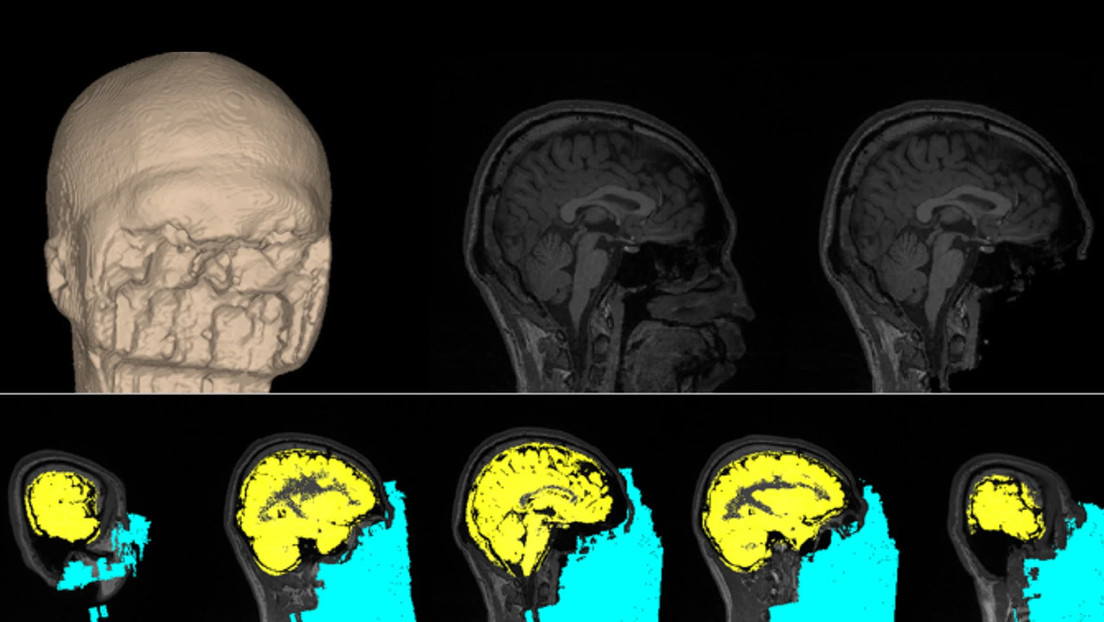

Además, el grupo de investigación creó una base de datos de imágenes neurológicas de los más de 60 individuos que se sometieron al experimento. Esta base de datos consta de imágenes estructurales y funcionales del cerebro, decodificadores de aprendizaje automático y datos procesados adicionales.